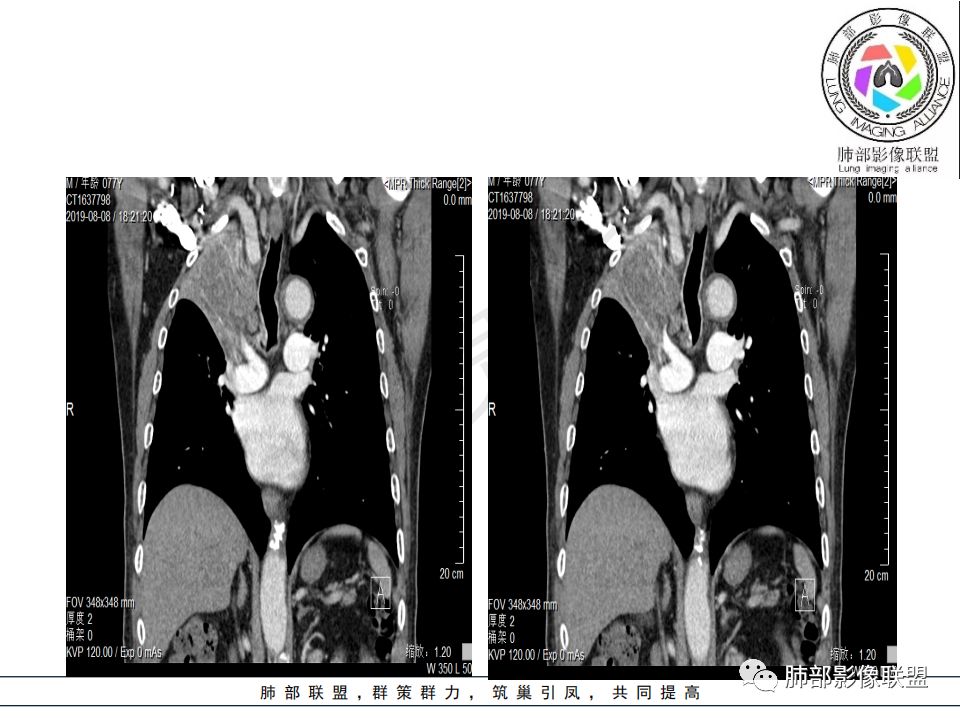

尘缘:

从强化情况和冠状位看主要还是从外向内的一个肿块,有不张,但不张范围不大,近端支气管堵塞,考虑腺癌或类癌(原发或转移都可能),鉴别鳞癌。

@曹坤,河北保定清苑区人民医院ct室 肿块大,阻塞和不张范围小,强化这么大肿块没有明显坏死,鳞癌这样相对少见了

@刘鋆(福州长乐区医院)影像科 转移啊,腔外都在生长,部分通过支气管壁进入腔内

@刘鋆(福州长乐区医院)影像科 先转移生长到外面,然后进入腔内生长,也是外朝内一种,与平时那种外朝内生长逐渐侵犯近端气管没有太多区别,只不过这个是转移而已。